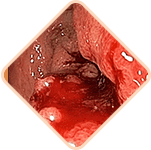

Sensación de pesadez o cuerpo extraño en el recto

Picazón y ardor en el área del ano

Dolor al defecar, caminar y sentarse

Sensibilidad de los ganglios hemorroidales al palpar

Sangrado durante los movimientos intestinales o con esfuerzo

Las heces contienen una cantidad gigantesca de gérmenes, bacterias y hongos. Si la infección ingresa al tejido pélvico y a los órganos vecinos, es posibleuna inflamación peligrosa y una infección de la sangre

Los vasos llenos del bulto hemorroidal son muy débiles. A menudo se rompen. El grado de pérdida de sangre en este caso puede ser tal que sea necesario transfusión de sangre

Se forman coágulos de sangre en los vasos. Estos coágulos de sangre pueden desprenderse y obstruir los vasos de los órganos internos, interrumpir la circulación sanguínea y causar un bloqueo en las arterias pulmonares.La probabilidad de muerte es alta.